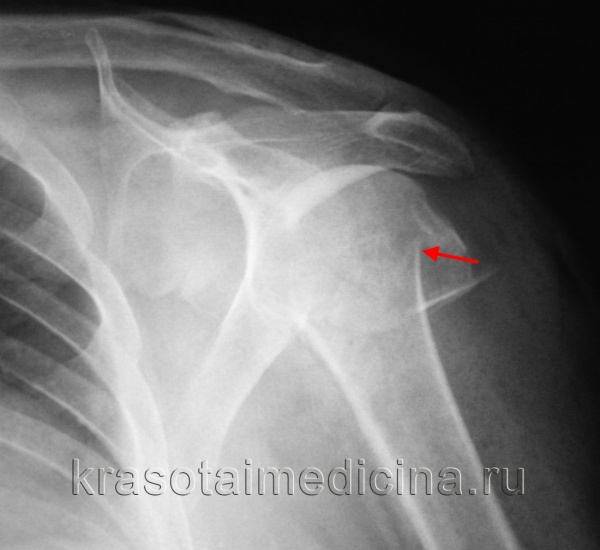

Переломы шейки лопатки. Переломы шейки лопатки тоже практически всегда сопровождаются смещением отломков кости. В тех случаях, когда смещение превышает 10 миллиметров, или если наклон суставной впадины лопатки в результате перелома изменился более чем на 40 градусов (вокруг вертикальной или саггитальной осей), для максимального восстановления функции необходима операция, в ходе которой устраняют смещение и фиксируют лопатку металлическими конструкциями. Если не устранить смещение костных отломков, то в последующем это может привести к нестабильности плечевого сустава (будут происходить вывихи), импинджемент-синдрому, нарушению функции вращательной манжеты.

Для фиксации отломков при переломе шейки лопатки чаще всего используют пластины и винты. В зависимости от линии перелома может потребоваться длинная пластина, располагающаяся по всему наружному краю лопатки или короткая.

Если перелом шейки лопатки сочетается с переломом ключицы и разрывом клювовидно-ключичных связок, то это приводит к появлению такого феномена, как флотирующая (болтающаяся) лопатка. В таких случаях также целесообразно оперативное лечение, в ходе которого фиксируют не только шейку лопатки, но и ключицу.

Слева – стабильный перелом лопатки, справа – нестабильный перелом лопатки (поврежден верхний поддерживающий комплекс плеча, т.е. имеется перелом ключицы и/или разрыв клювовидно-ключичных связок, характеризующийся вывихом акромиального конца ключицы)